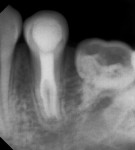

A 14-year-old female patient was referred to the endodontic specialization clinic of the Dentistry College of Recife in Brazil for endodontic treatment of tooth No. 21. During the anamnesis, the patient reported having had a history of painful symptoms in this tooth. Clinical examination revealed negative responses to thermal testing in cold mode (Endo-Ice, Coltene, coltene.com), percussion, palpation, and mobility testing. Upon periapical radiographic examination, the presence of a radiolucent image, suggestive of a periapical lesion, was verified, and an atypical anatomy was associated with the tooth in question (Figure 1). A CBCT was then taken in order to obtain a more in-depth and accurate diagnosis; it demonstrated the presence of a C-shaped canal (Figure 2 through Figure 4). The resulting diagnosis showed asymptomatic apical periodontitis. The endodontic treatment would be performed in two sessions.

According to Patel et al, the 3-dimensional radiographic evaluation of teeth and their adjacent structures based on the use of CBCT is desirable to assist in the diagnosis and/or treatment of anatomical complexities.19 The limitations of conventional radiography are well established, such as the restrictions of viewing a 3-dimensional structure in only two dimensions, the masking of areas of interest, and image distortions. These shortcomings are reflected in inaccurate diagnoses of morphological changes, thus restricting the choice of the treatment planning.20 Consequently, the use of CBCT, as demonstrated in the present case, is essential, as the superior visualization of the internal and external anatomy and the perception of the configuration of the "C" canal in three dimensions increased the predictability of the treatment.